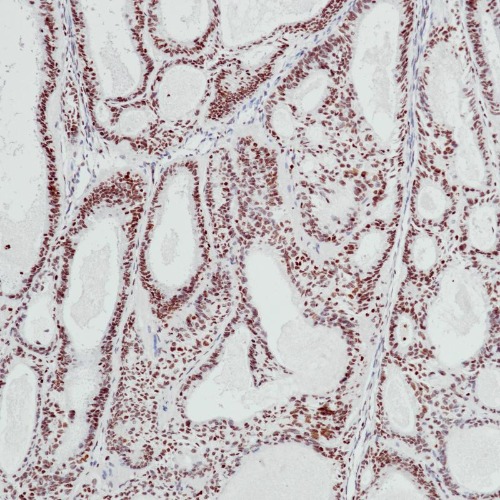

Immunohistochemical staining of human endometrial cancer tissue using BCOR Monoclonal Antibody(ARB595)